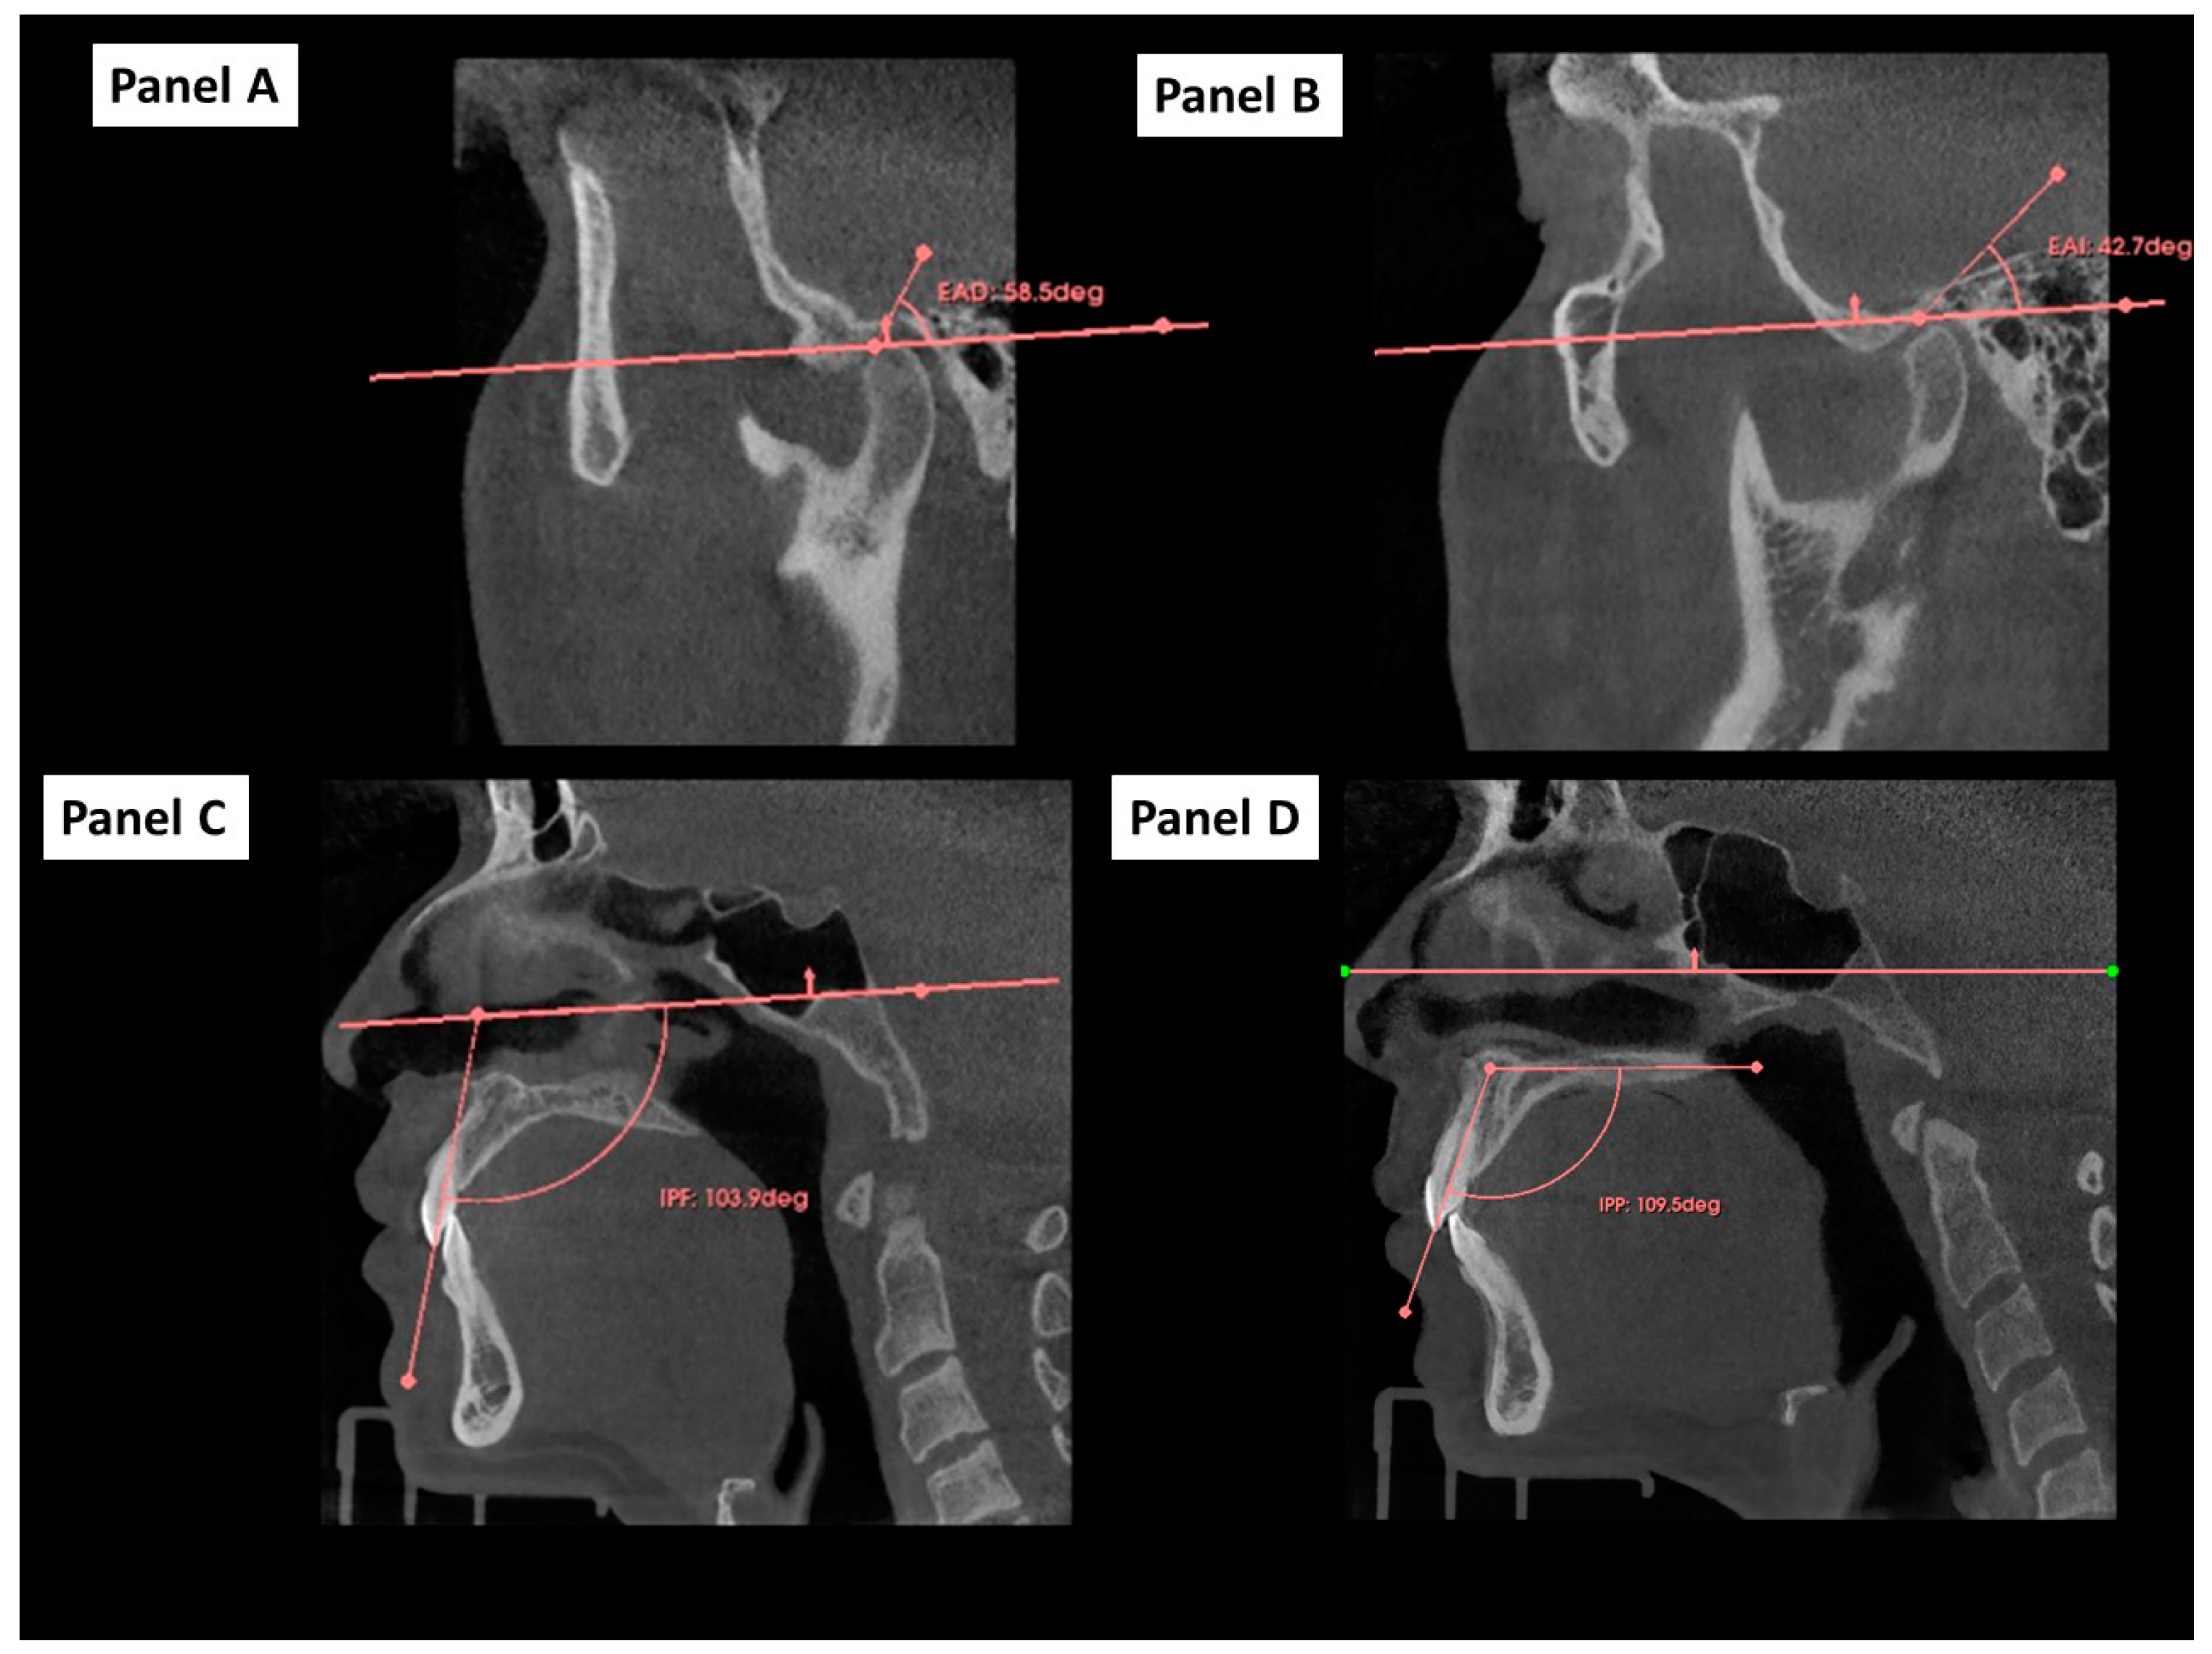

2.4. Outcome and Independent Variables

2.5. Cephalometric 2D Variables